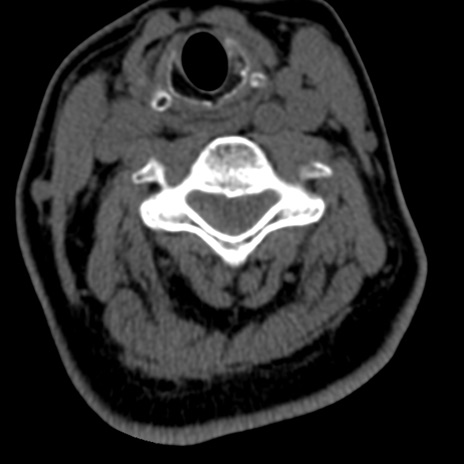

症例50 頚椎CT(横断像)

矢状断像